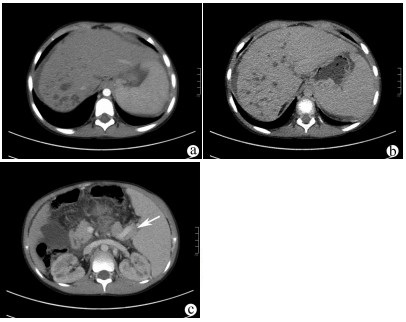

高原地区体外肝切除联合自体肝移植术治疗晚期肝泡型包虫病的术后并发症及其防治策略

田青山, 冯少培, 郭亚民, 韩秀敏, 赵顺云, 叶成杰, 安永德, 吴世乐, 王向前, 郑海波, 朱文君, 阿吉德, 高伟, 潘洪帅

2021, 37(9): 2153-2160. DOI: 10.3969/j.issn.1001-5256.2021.09.029

摘要(1294) HTML (489) PDF (3321KB)(54)

摘要:

目的  探讨高原地区体外肝切除联合自体肝移植术治疗终末期肝泡型包虫病的术后并发症并探讨防治策略。  方法  收集青海省人民医院2013年1月— 2019年3月接受自体肝移植术的11例终末期肝泡型包虫病患者的手术资料及随访资料,对术中及术后情况进行分析。  结果  11例患者均成功行自体肝移植术,无术中死亡,其中2例(18.18%)行半离体肝切除,9例(81.82%)行全离体肝切除。肝后下腔静脉重建方式中,采用自体大隐静脉进行重建者2例(18.18%),采用人造血管重建者4例(36.36%),5例(45.45%)保留自体肝后下腔静脉。胆道重建方式中,8例(72.73%)行胆肠吻合术,3例(27.27%)行胆管端端吻合术。11例患者的术后并发症主要有出血2例(18.18%);胆汁漏、腹腔感染4例(36.36%),胆肠吻合口狭窄1例(9.09%), 血栓2例(18.18%),肺部感染、胸腔积液2例(18.18%);包虫复发1例(9.09%)。11例患者发生围术期死亡2例(18.18%),其余9例(81.82%)患者均好转出院。  结论  出血、胆道并发症和感染是造成高原地区自体肝移植患者死亡的主要原因,精准把握手术适应证、术前仔细多学科评估、术中精湛的操作、外科技术流程的标准化及精细的围术期管理是降低自体肝移植术围术期病死率、避免和减少术后并发症以及使患者获得长期良好生存的关键。